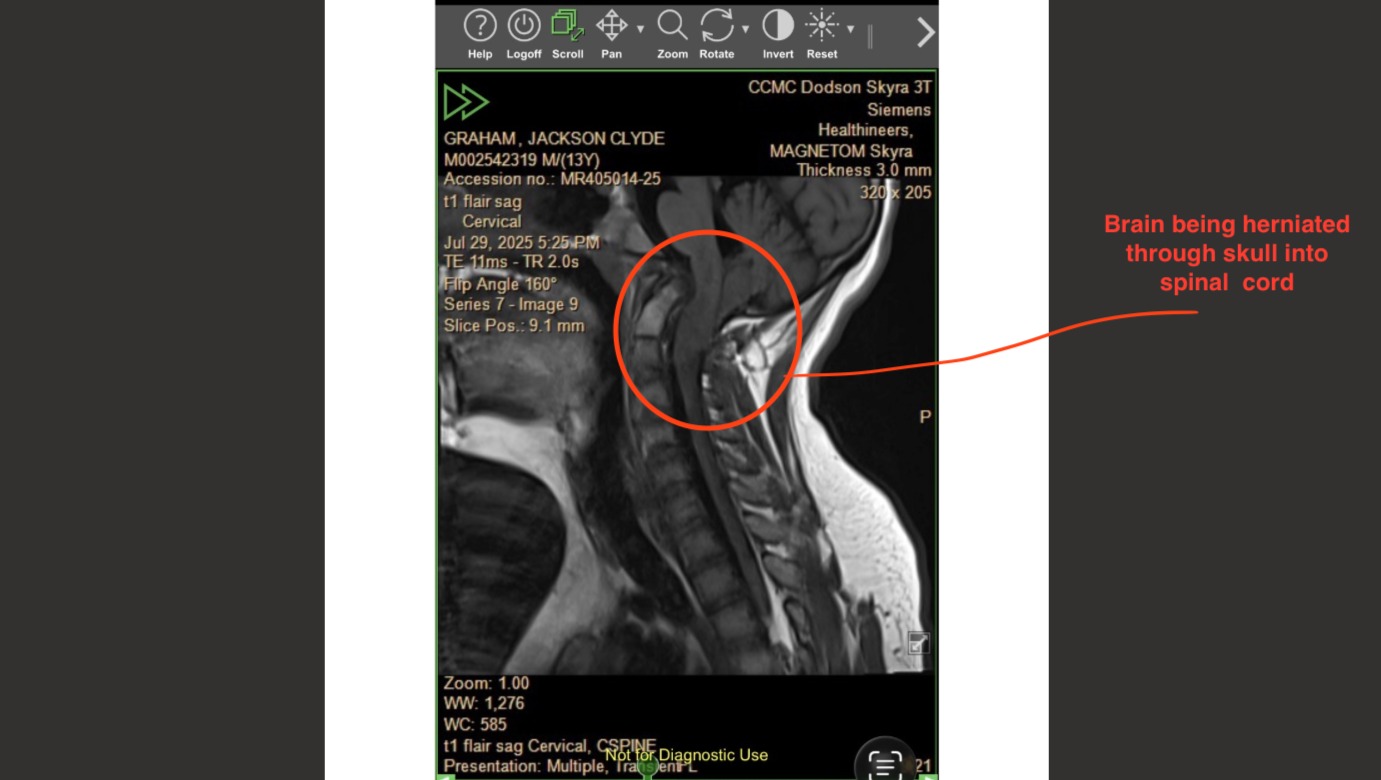

Jackson was born with a rare genetic disorder called Wiedemann–Steiner Syndrome, which he was diagnosed with four years ago. Along with that diagnosis came many serious medical challenges, including severe scoliosis, bone abnormalities, fused vertebrae in his neck, sleep apnea, and most critically, a complex Chiari malformation. This means part of his brain is being pushed down through the base of his skull, leaving very little room for his brain and causing dangerous compression of his brainstem.

Over the past year, Jackson’s symptoms have increased significantly and are now affecting his quality of life at just 14 years old. He deals daily with intense head pressure and headaches, dizziness, ringing in his ears, chronic back pain, and fatigue. Things no child should have to live with.

Because Jackson’s case is so severe, he must be treated by a highly specialized pediatric neurosurgeon. Unfortunately, there are no surgeons in Texas who perform the type of surgeries he is needing. By the grace of God, Jackson is now under the care of Dr. Jeffrey Greenfield at Weill Cornell in New York City, one of the leading pediatric Chiari specialists in the country. Jackson is tentatively scheduled for surgery this summer, and this long-awaited procedure could truly change his life.